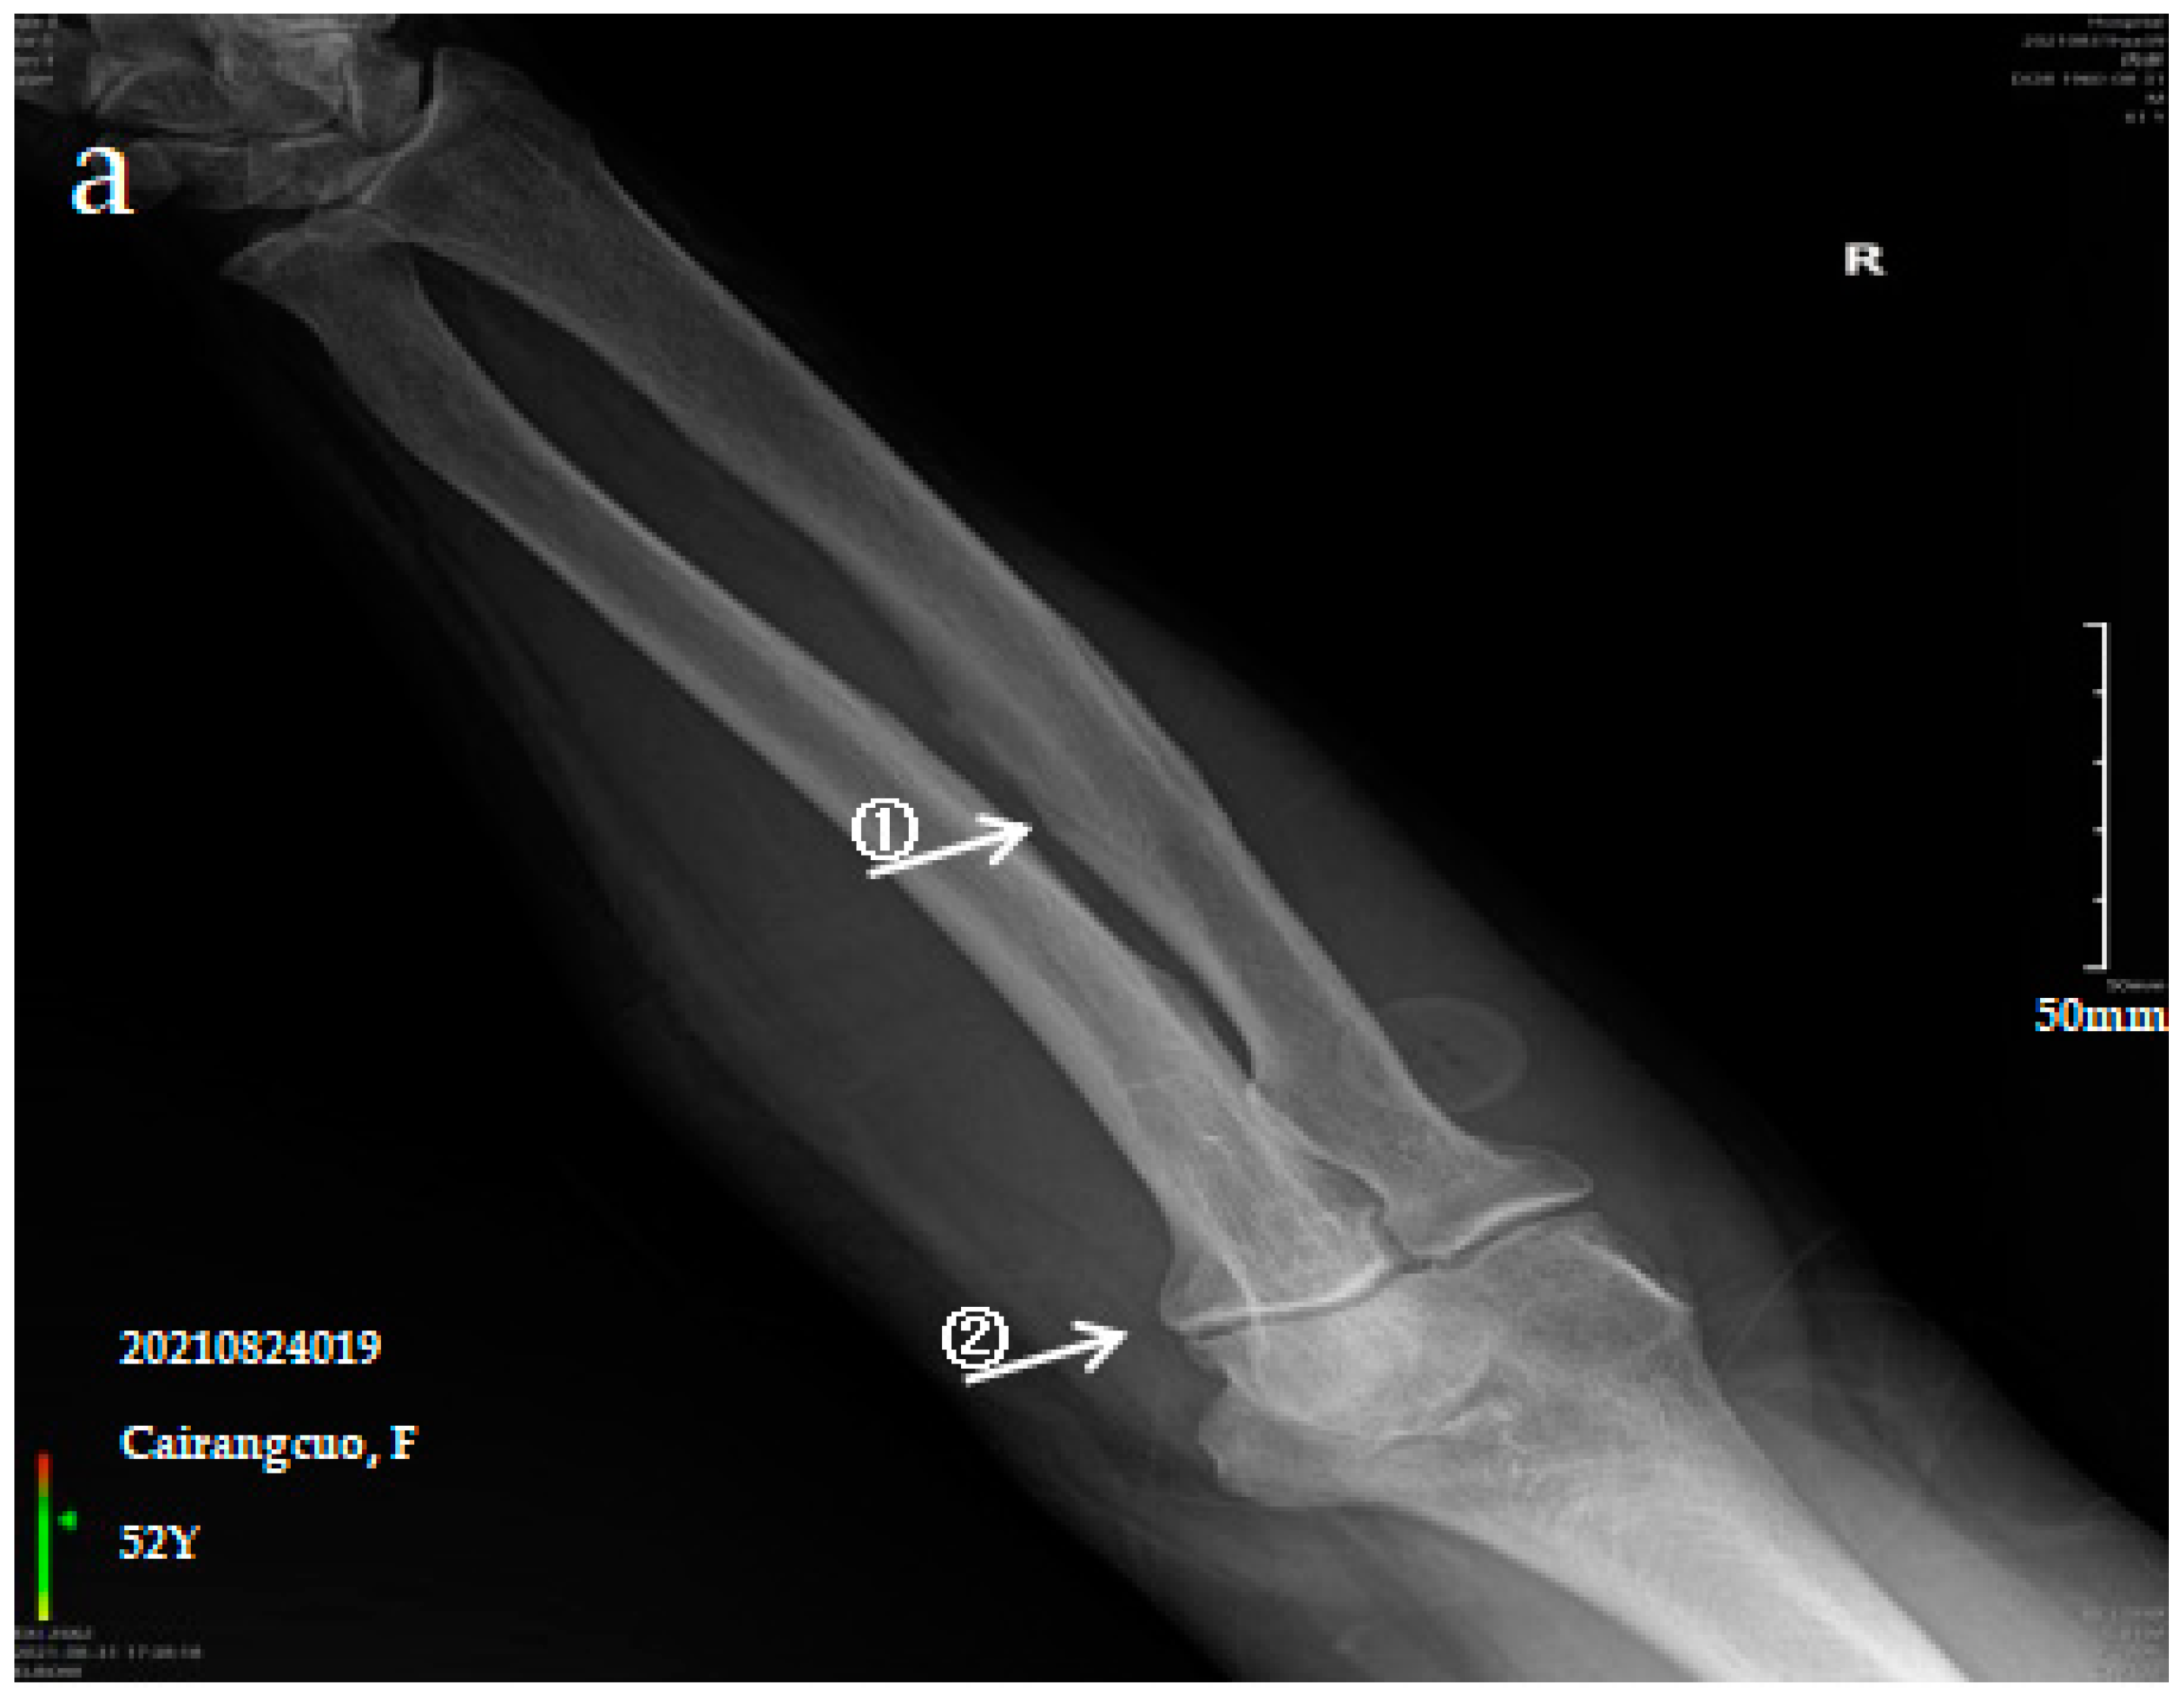

3.2.1. Case Analysis of a Patient Diagnosed by X-ray with Mild SF